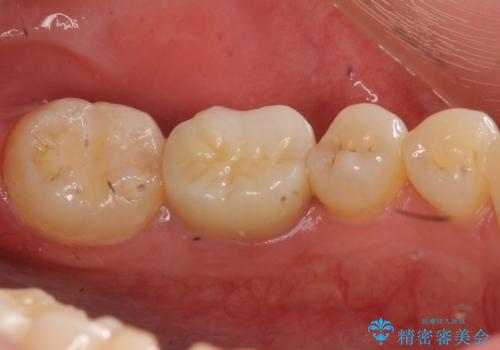

- 右下の奥歯が欠けたとのことで来院されました。

診てみると奥歯の詰め物が欠けていることが分かりました。

噛みしめが強く、元の詰め物の大きさが大きかったため今回は被せ物での治療をすることとなりました。

欠けた詰め物をすべて取り除くと深いところに取り残された虫歯を発見しました。

虫歯の除去後は残った歯の厚みが薄くなっていたため、今後の破折リスクを考慮してクラウンでの修復処置となりました。

虫歯が深く歯の神経の炎症が予想される箇所には鎮静作用のあるセメントを敷き、経過をみた後に被せ物をセットしました。

写真・レントゲン画像からもわかる通り、適合の良いクラウンを入れることができました。